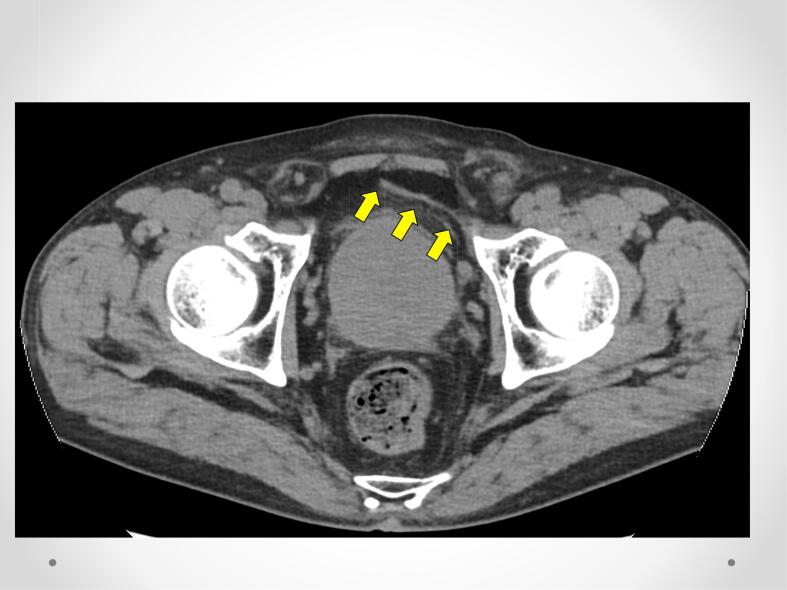

Physical examination and abdominal computed tomography revealed recurrent inguinal hernia with cord lipoma (Fig. 1). We were thinking this recurrent case was difficult. So using the Da Vinci Xi (Intuitive Surgical Inc. Sunnyvale CA) robot, R-TAPP was performed for recurrent left inguinal hernia, which developed after Kugel hernioplasty. The robot was positioned to the left of the patient. We used three robotic ports as the three arms for a bipolar fenestrated grasper, monopolar scissors, and suture cut needle driver (Fig. 2).

Fig. 1.

Abdominal computed tomography.

The last mesh was detected on the membrane of the bladder.

The left recurrent inguinal hernia was suspected to be fatty tissue.